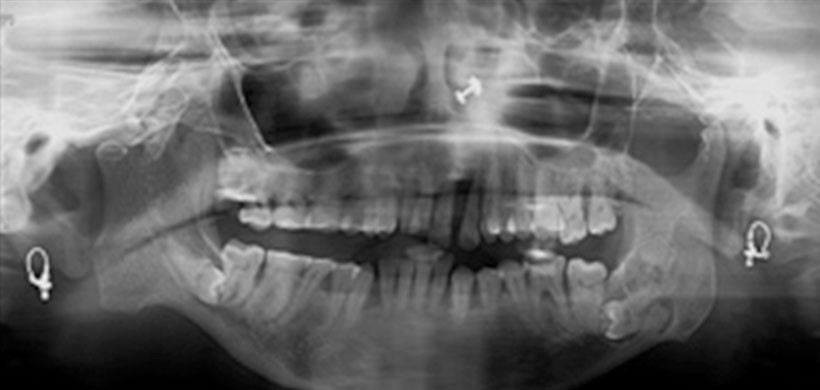

Posteriormente se realizó una ortopantomografía [Figura-3] que reveló una impactación en posición horizontal de las piezas 38 y 48. Así como una imagen radiolucida que rodea la región periapical de la pieza 38. También se encontró un aplanamiento de la cabeza del cóndilo mandibular izquierdo y una alteración de la morfología del cuello y cóndilo mandibular derecho en donde la escotadura sigmoidea mostró una curvatura reducida junto a una muesca prominente antegonial.

Figura 3: Radiografía panorámica